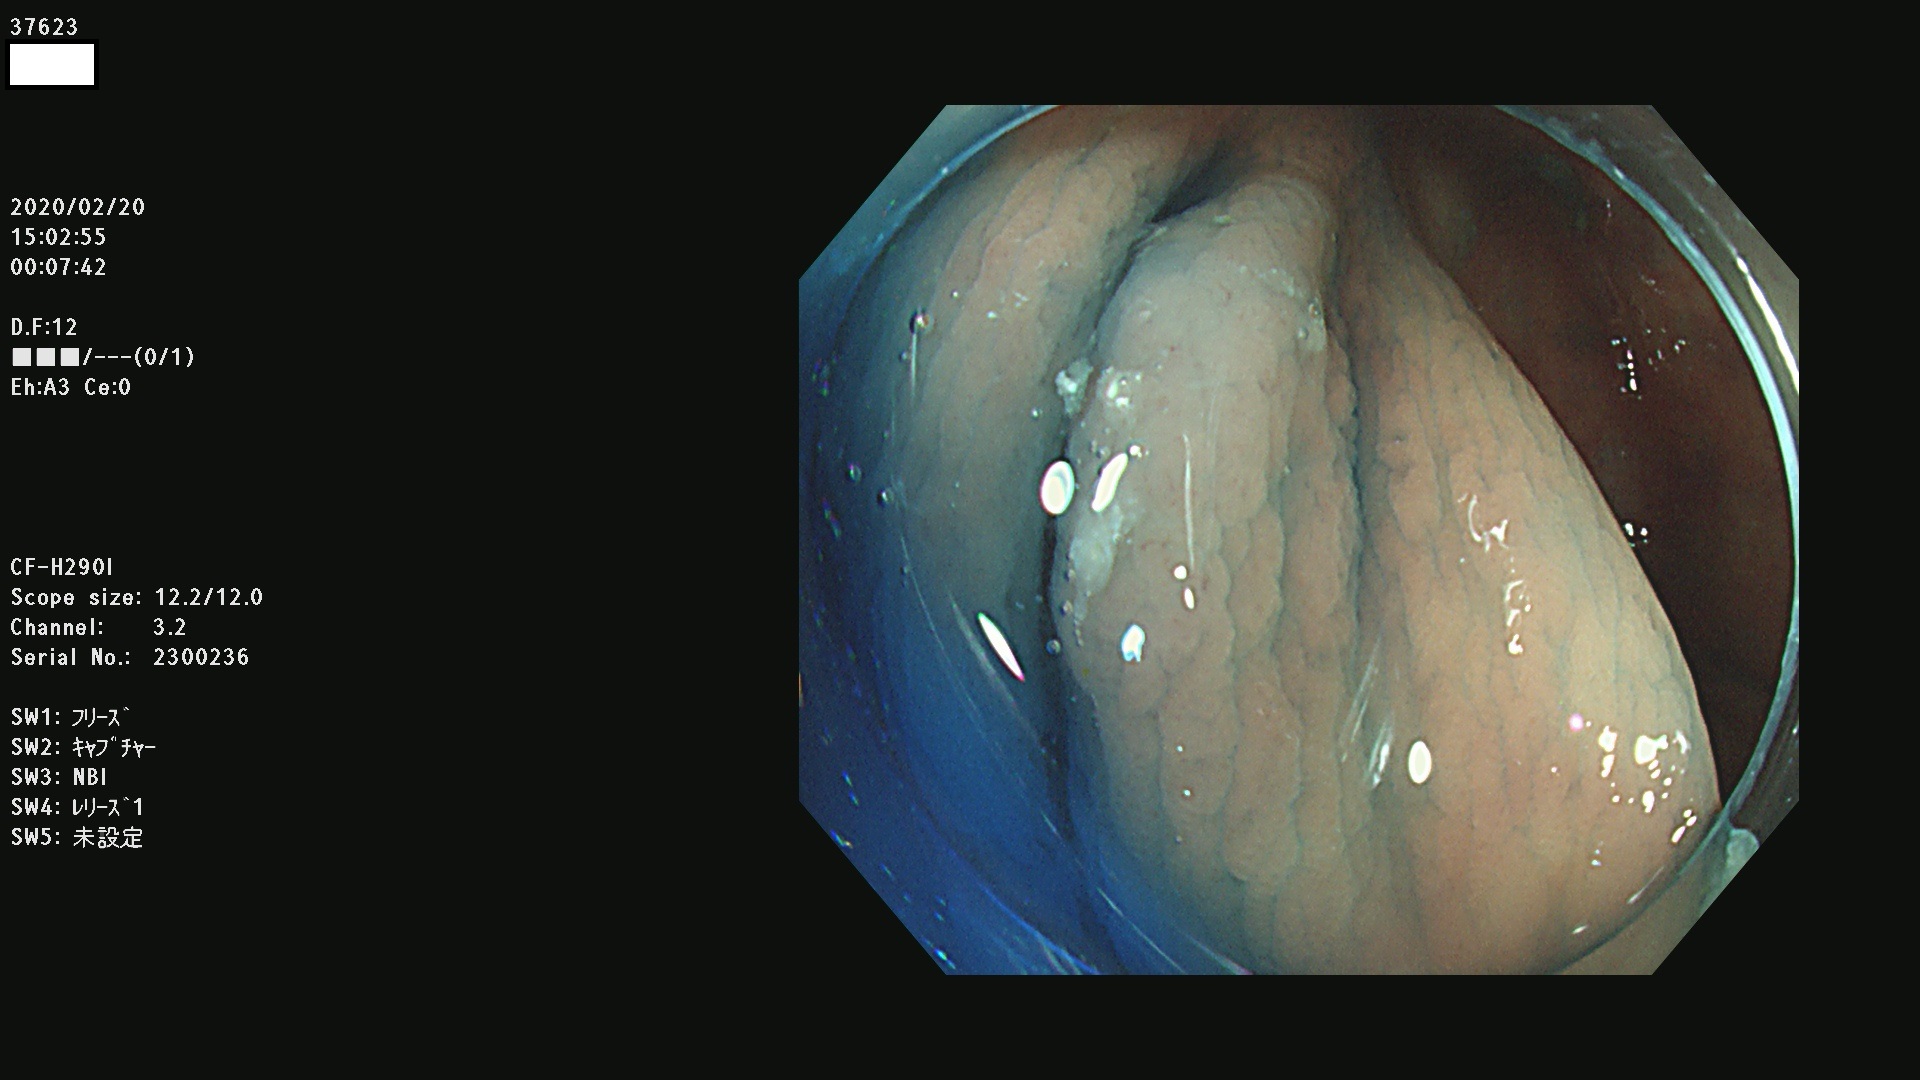

37600 37601 37602 37603 37604 37605 37606 37607 37608 37612 37614 37616 37618 37619 37620 37621 37622(SSAPのみ) 37623(SSAPのみ) 37624 37626 37627 37628 37629 37632 37633 37635 37636(SSAPのみ) 37639 37640 37641 37642 37643 37644 37647(SSAPのみ) 37648 37649 37650 37652 37653 37655 37657 37659 37660 37662 37664 37666 37668(SSAPのみ) 37670 37671 37672 37676 37677 37678 37679 37680 37682 37684 37685(SSAPのみ) 37686 37687 37688 37689 37690 37691 37692(SSAPのみ) 37693 37694 37695 37696 37697 37699

発見困難で危険性の高い平坦型病変(上記100名より抽出)